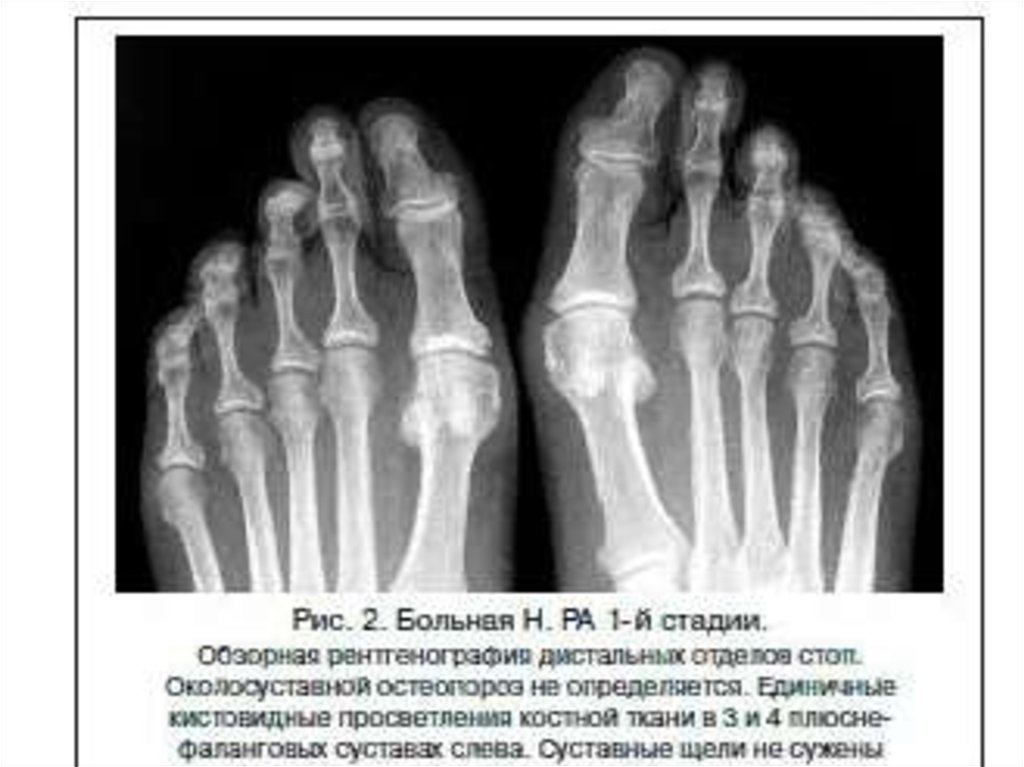

Рентгенодиагностика артрита

1. Рентгенодиагностика артрита